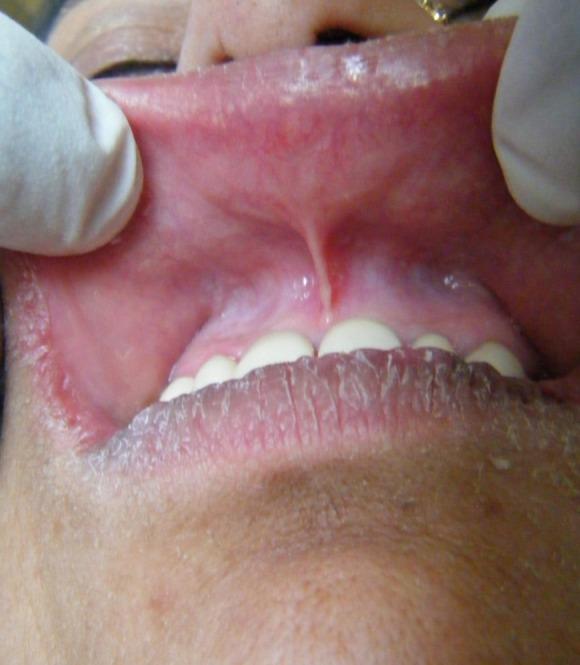

Burning mouth syndrome (BMS) is a relatively common disease that can severely affect the quality of life of the patient. It causes chronic orofacial pain or oral burning sensation even in the absence of any detectable organic cause. The etiology of BMS is complex and multifactorial. It has been associated with menopause, trigger events and even genetic polymorphisms. Although its etiology remains unclear, there is still much evidence that psychological elements like stress, anxiety or depression do play a significant role. There are several studies in the literature which only report the association of BMS with psychological factors. But to the best of our knowledge, there is no such case reported in the literature which has actually highlighted the management of such a case with psychogenic elements involved. In this case report, apart from discussing the role of psychological factors, the treatment of BMS with emphasis on counseling is also emphasized. Further, it is of interest to know that such patients with psychologically induced burning mouth syndrome have to be evaluated to their deepest details. Even their commonly overlooked gestures and habits like watching a particular television soap opera may be involved in their disease process. It can be concluded that psychological counseling in general dental practice can provide an effective cure for chronic oral burning sensation with psychological factors involved.